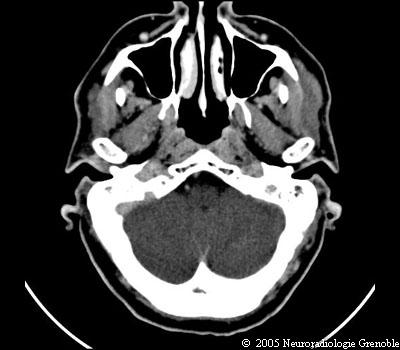

Radioanatomie TDM de l'encéphale

TDM cérébrale sans injection